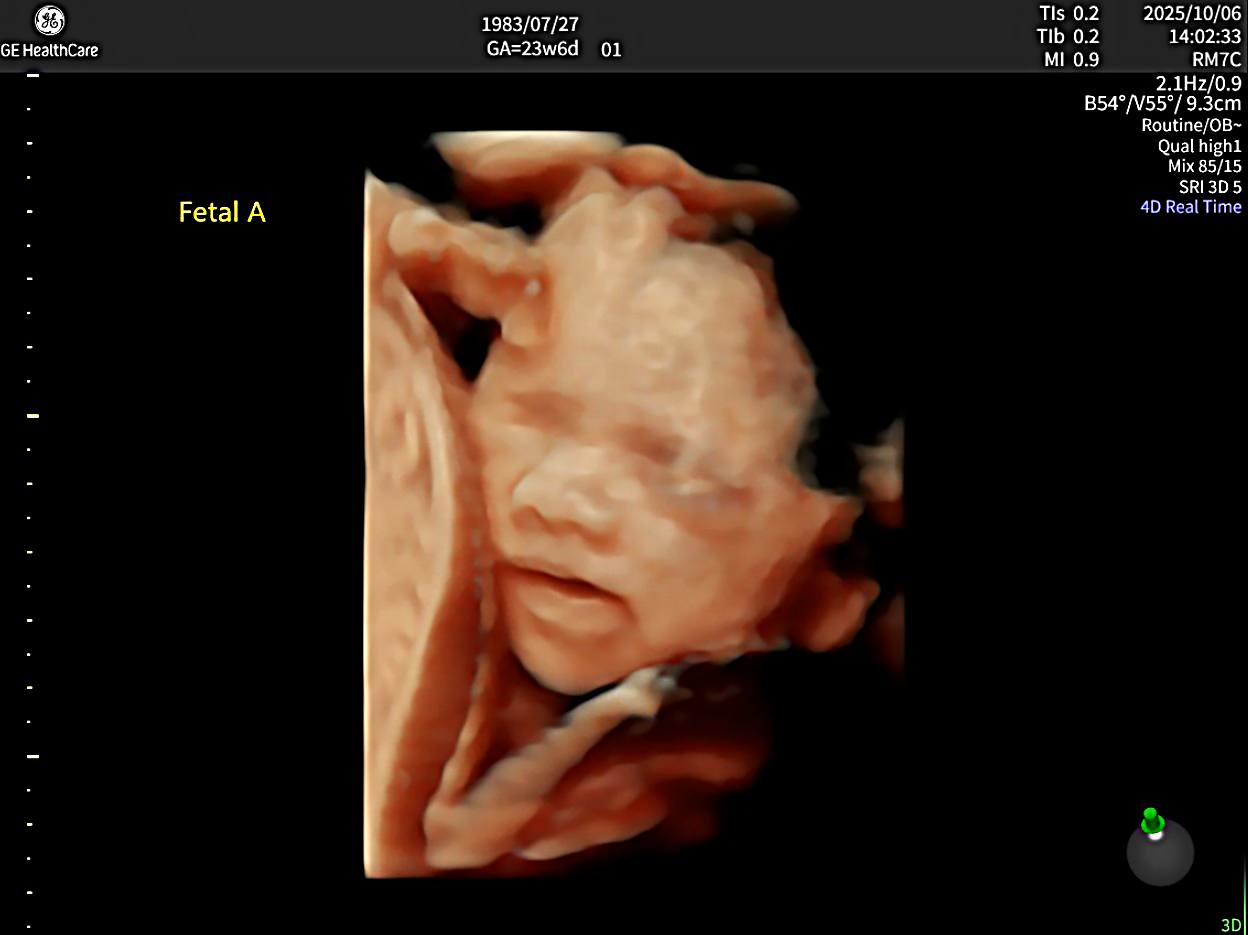

4D超音波其實就是在3D立體影像的基礎上加入「時間軸」,讓影像變成即時動態畫面,因此可以清楚看到胎兒在子宮中的動作,例如:寶寶打呵欠、吸手指或揮動手腳等可愛畫面,許多孕婦會安排胎兒4D超音波來記錄寶寶在子宮中的模樣。

一般建議的4D超音波週數大約落在懷孕24~32週之間,此時胎兒脂肪逐漸增加,臉部輪廓較清晰,也是多數人安排4d超音波何時照時常見的時間點。

4D超音波在什麼週數適合照呢?如果是產檢時希望能將胎兒在肚子裡的可愛模樣拍攝下來留念,建議4D超音波的拍攝時間點可以選在26週到32週之間。

- 在26週之後胎兒五官樣貌已經逐漸成形,這時候子宮內還有空間可以活動,較容易拍攝到臉部表情及吸吮拇指等等動作。

- 當週數來到32週以後,由於體積變大導致寶寶在子宮內活動空間變小,胎兒動作可能會減少,較難拍到連續的動作或表情。

同時,系統也具備即時3D與4D胎兒超音波成像能力,能清楚呈現寶寶臉部輪廓與動態表情,例如:打呵欠、吸手指或微笑等畫面,讓準爸媽在進行胎兒4d超音波時,也能留下更清晰立體的珍貴影像。